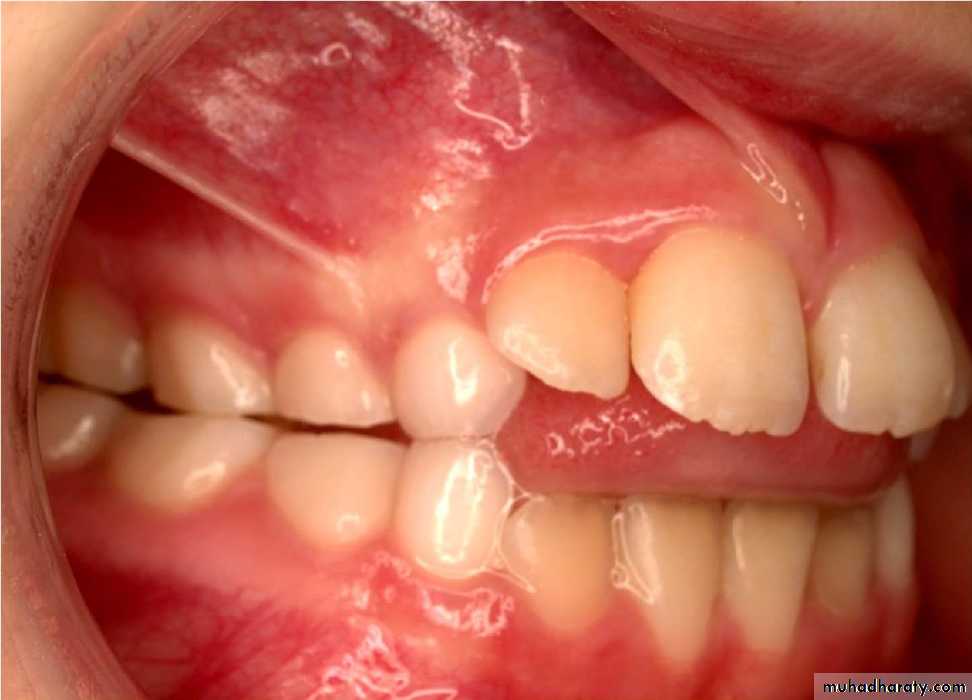

b. Tongue thrust: placement of the tongue tip forcefully forward between the upper and lower incisors during swallowing.1. Anterior open bite

2. Proclination of anterior teeth

3. Increased overjet

4. Class II malocclusion